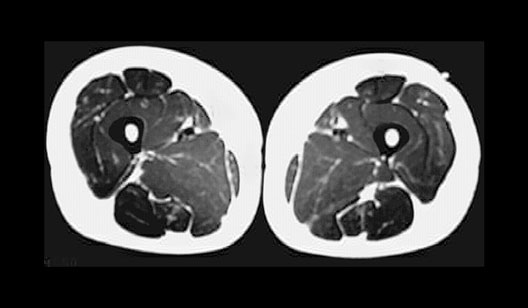

Thigh Cross Section

Roll mouse over image to display labels.

1. Quadriceps

2. Sartorius

3. Adductor canal

4. Adductors

5. Hamstrings

6. Femur